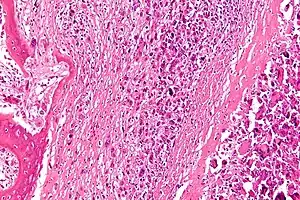

Micrograph of an osteosarcoma, a malignant primary bone tumor.